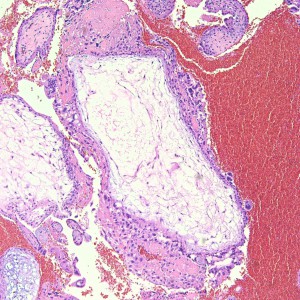

On higher power, we can see that this nodule is mostly composed of this pink amorphous material with interspersed large, round cells with abundant eosinophilic and sometimes clear cytoplasm (arrows). There are essentially no mitoses and atypia is not very prominent.

On higher power of the acellular areas we can see vague outlines of the cells that may have been there and have now degenerated into this hyalinized stroma (black arrows). The cells that remain are large, round to oval, with dense eosinophilic to clear cytoplasm (red arrows).